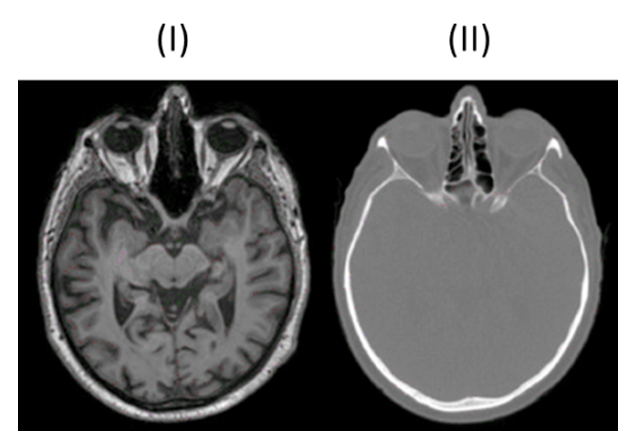

MRT (Bild I)

Strahlenfrei

hohe Bildqualität

Weichteildarstellung

Flexibilität bei Schnittführung

MRT (Bild I) typische Merkmale

Erzeugung Graustufenbildern basierend auf Anregung der Wasserstoffprotonen im Gewebe

T1-Wichtung: Hervorhebung fetthaltiger Strukturen → Knochen schwarz, Fettgewebe weiß

T2-Wichtung: Hervorhebung wasserhaltiger Strukturen → Liquor weiß, weiße Substanz dunkelgrau

CT (Bild II)

CT (Bild II) typische Merkmale

Weniger Kontrast bei Weichgewebe

Weiße Knochen